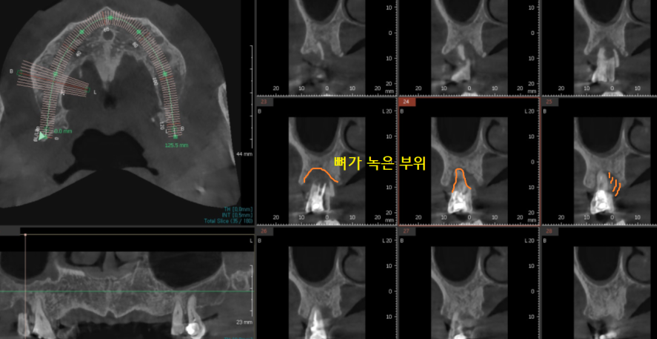

임플란트 진단을 위해 ct를 찍어보았는데

다른 치아도 뼈가 많이 녹은 것이 발견

환자분께 안 좋은 상황임을 안내해드렸습니다.

231211

부러진 치아 바로 옆에였는데요.

하셨던 아말감 충전된 상태도 안좋았지만

잇몸 뼈가 많이 녹으셨어요.

그렇다고 뽑기에는 아직 아쉽고

아까운 상태라

관리하면서 더 쓰시라고 말씀드렸습니다.